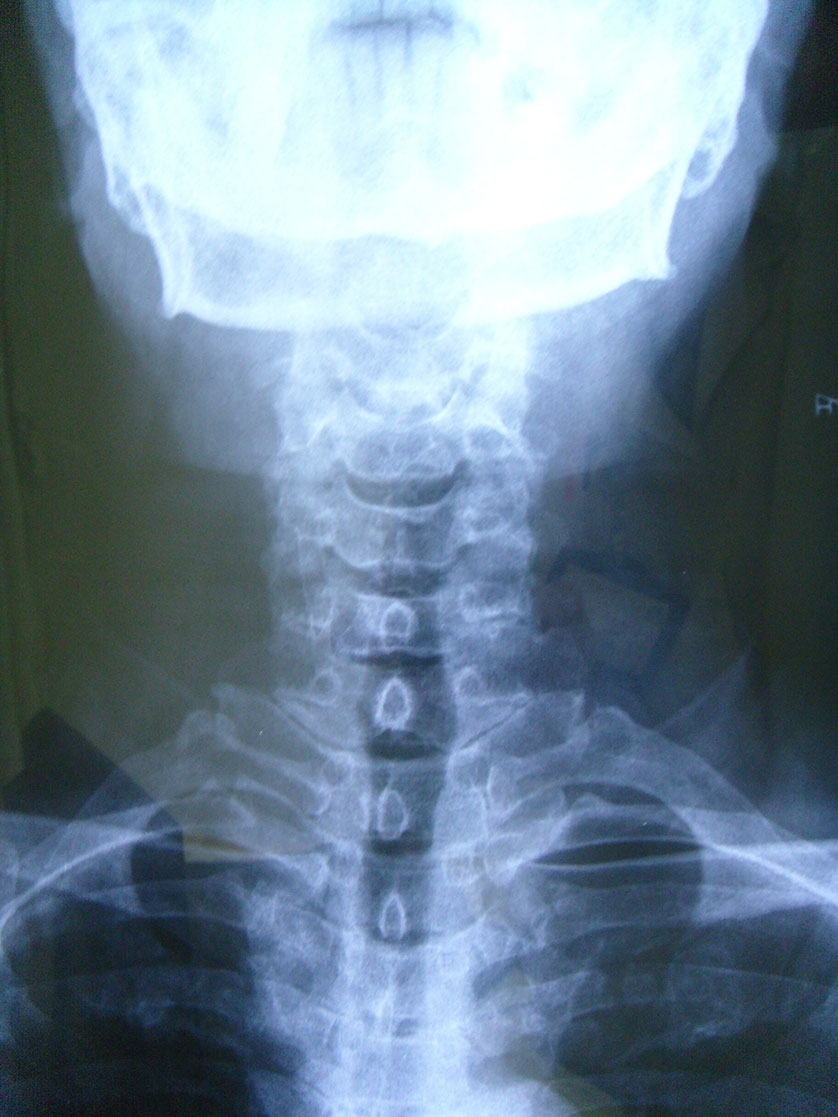

徐**,男性,于2006年2月24日因第3/4颈椎椎间盘突出症,颈椎前路椎间盘切除,同种异体骨椎体间植骨融合内固定手术,术后2个月,11个月及4年半随访植骨块愈合良好